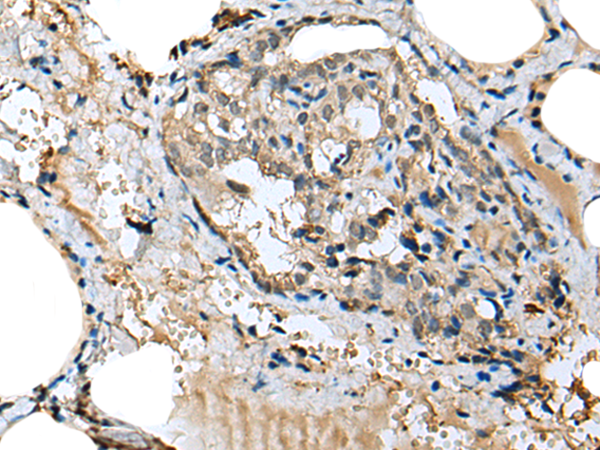

Product Image

The image is immunohistochemistry of paraffin-embedded Human brain tissue using (MIOX Antibody) at dilution 1/25. (Original magnification: ×200)

The image is immunohistochemistry of paraffin-embedded Human thyroid cancer tissue using (MIOX Antibody) at dilution 1/25. (Original magnification: ×200)